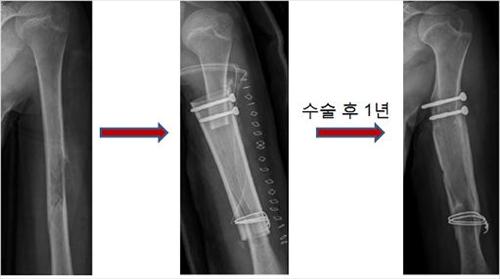

<Áßø ¹æ½Ä µ¿Á¾°ñ ÀÌ½Ä ÈÄ °æ°ú>